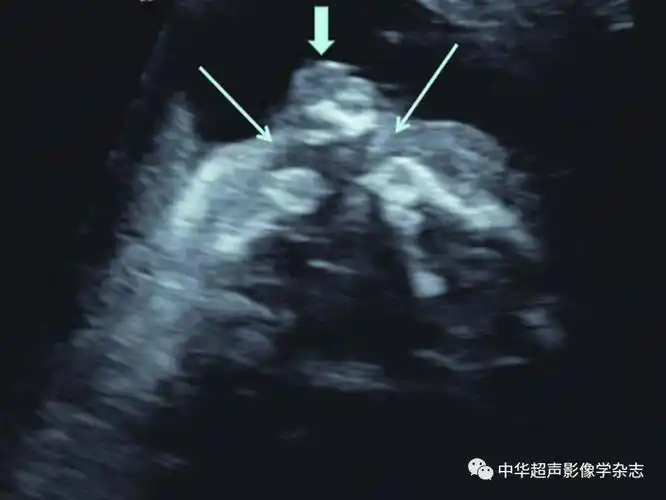

唇裂b超图侧面图

在妊娠20~24周超声检查时,应通过观察鼻唇冠状面判断上唇是否有唇裂

(箭头所示);b:正常胎儿面部正中矢状面下唇裂非常罕见且超声诊断困难